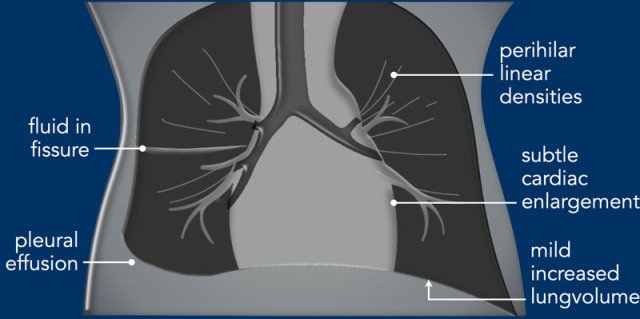

Transient tachypnea of the newborn is seen in full term neonates with mild respiratory distress and  presents with subtle increased lung volume, parahilar linear densities and pleural effusions.

Imaging

• Mild increased lung volume.

• Interstitial edema resulting in perihilar linear densities.

• Subtle enlargement of the cardiac silhouette.

• Pleural effusions and fluid in the fissures.

• The radiological findings may be asymmetrical.